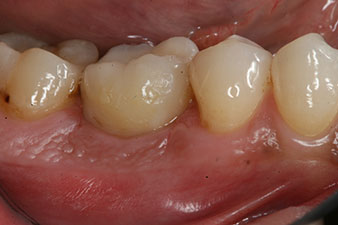

Les dernières photos montrent la couronne composite monolithique retenue par une vis une fois mise en place et la radio de contrôle (Fig. 9 et 10) (6).